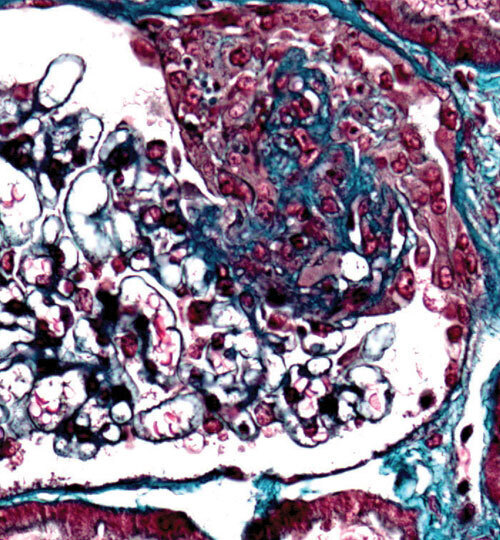

Les vascularites associées aux anticorps anticytoplasme des polynucléaires neutrophiles (ANCA) sont un groupe hétérogène de maladies inflammatoires touchant les vaisseaux de petit calibre. Les données épidémiologiques mettent en lumière l’influence de facteurs environnementaux et génétiques. Les progrès diagnostiques et thérapeutiques sont majeurs, améliorant le pronostic tout en réduisant la toxicité des traitements.